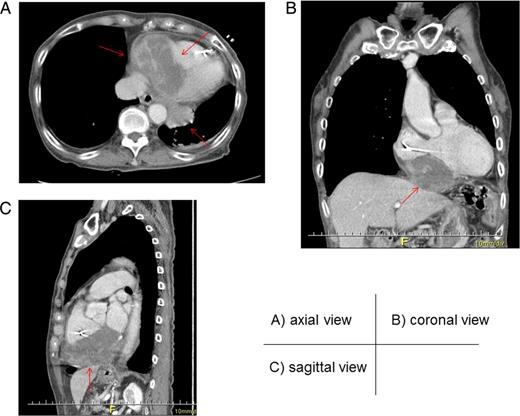

Axial (A), coronal (B) and sagittal (C) views of enhanced computed tomography. A tumor (arrow) measuring 90.0 × 56.4 × 60.0 mm, with heterogenous low enhancement and an unclear border invaded into the inferior myocardium.